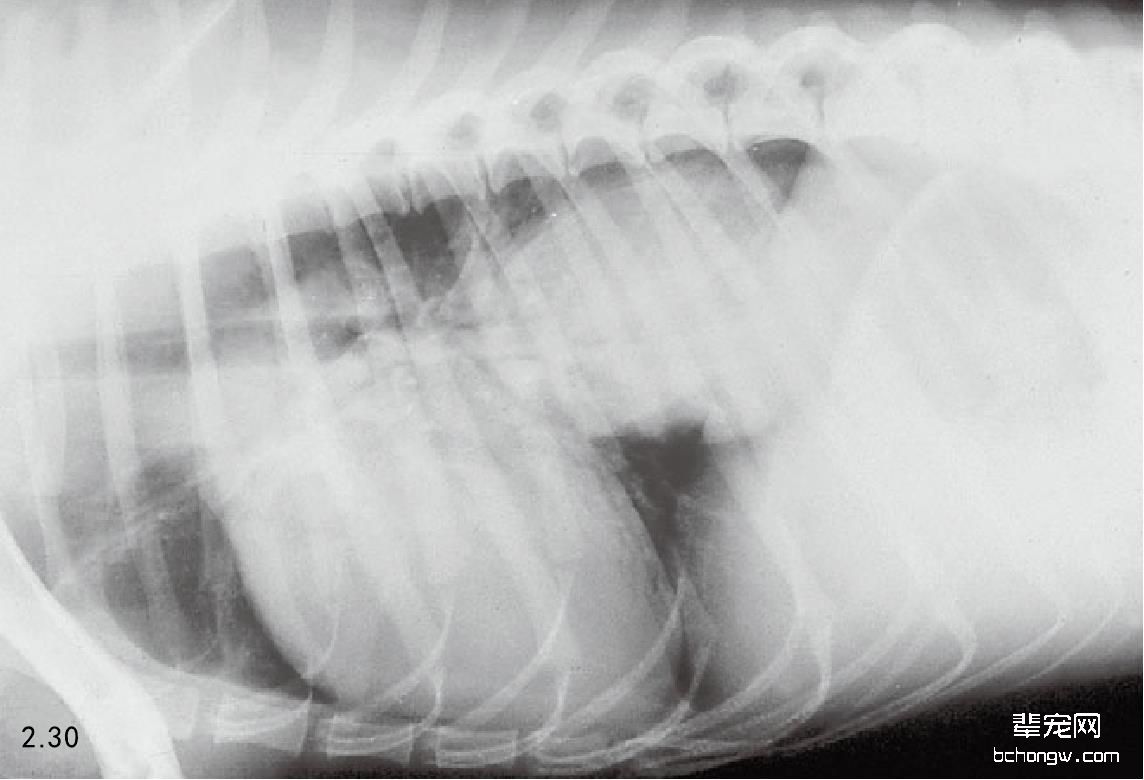

图2.30 患有肺部脓肿的2岁史宾格猎犬的侧面胸腔X线片。